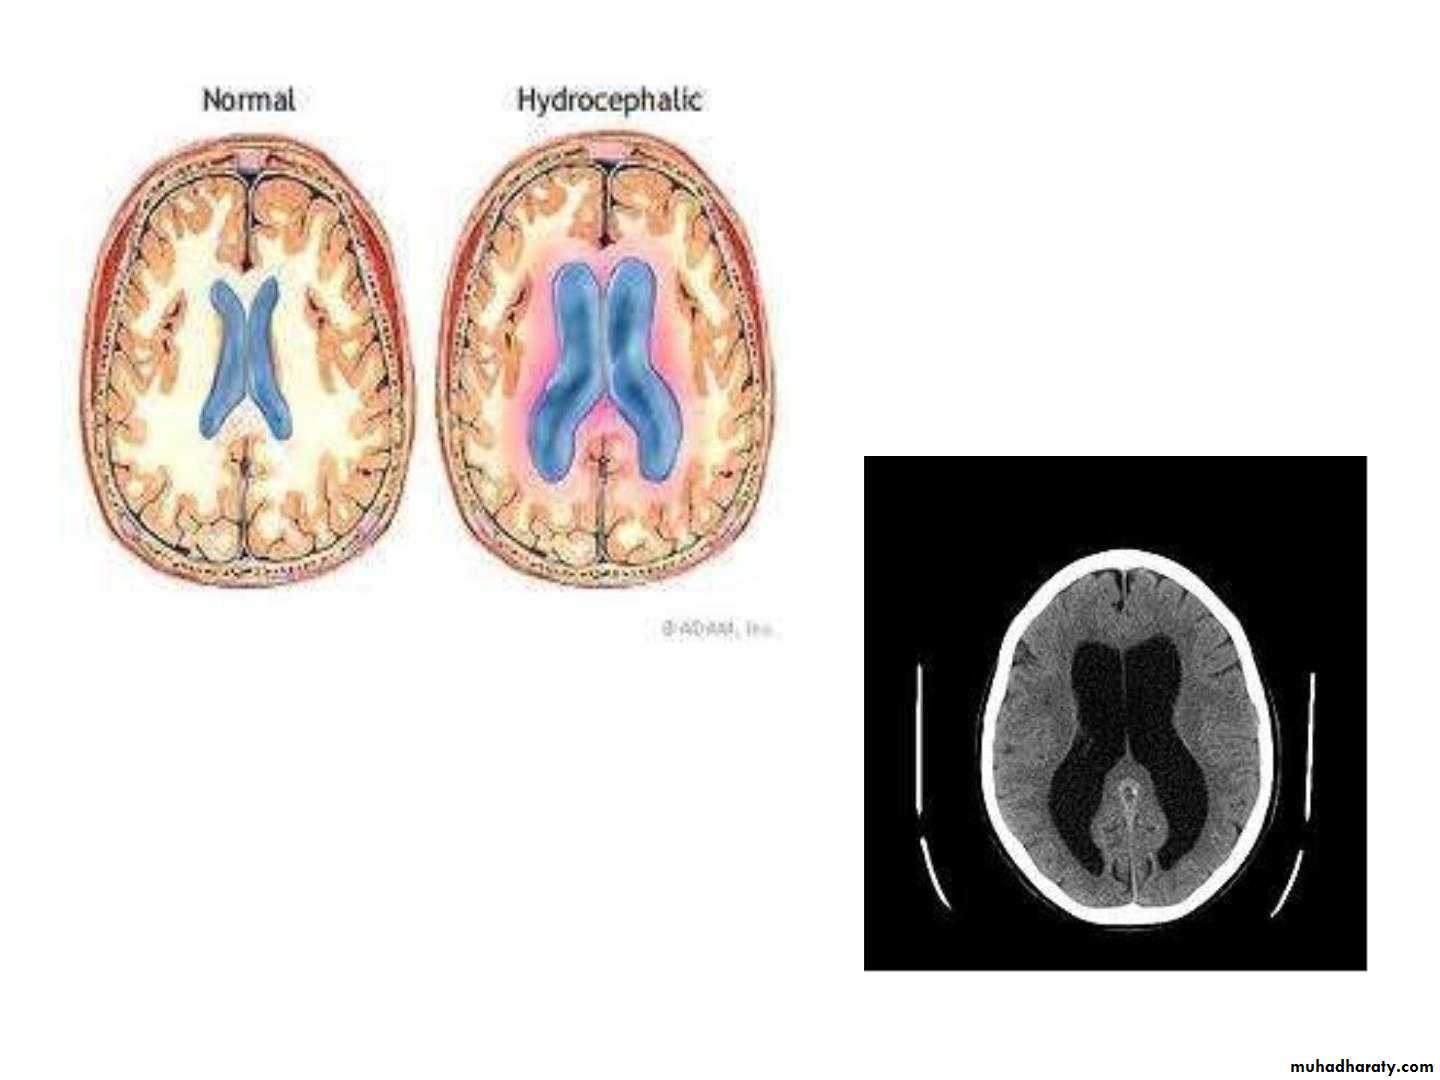

Hydrocephalus

• An abnormal increase in the volume of• CSF

• Symptoms: sleep changes, spastic

• paresis, papilledema, bulging of skull in

• young, seizures, cranial nerve deficits,

• depression.